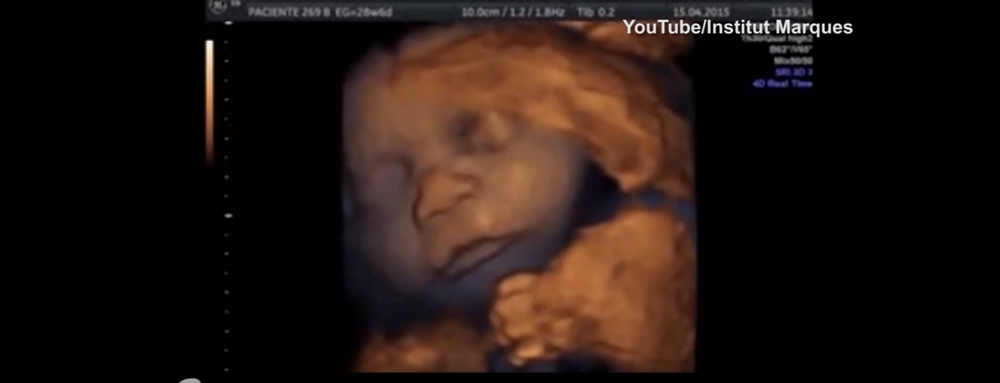

В 1989 году родился здоровый ребенок после того, как его мать, перенесла инсульт и была признана мёртвой из-за гибели мозга. Он пробыл в утробе женщины, подключенной к системе жизнеобеспечения, 107 дней.